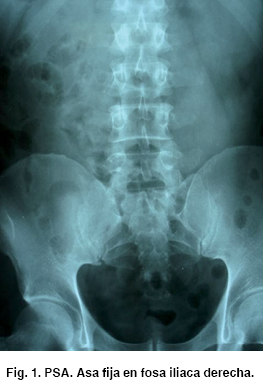

Se le toma una placa simple de abdomen evidenciando asa fija a nivel de fosa iliaca derecha (Figura 1).